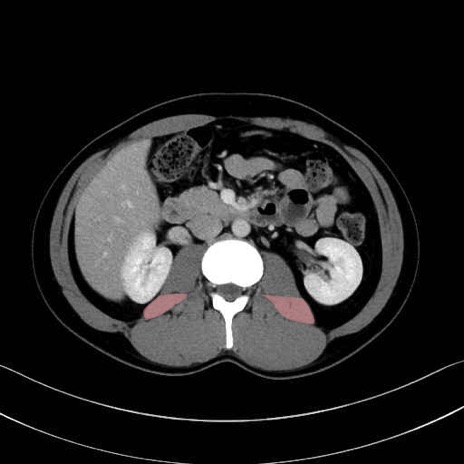

2. 腸腰筋群と骨盤底筋

大腰筋 (Psoas major)

腸骨筋 (Iliacus)